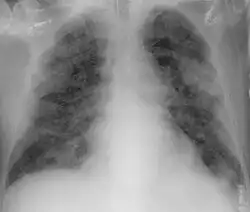

From the CT scans of COVID-19 infected lungs, white patches were observed containing fluid known as ground-glass opacity (GGO) or simply ground glass.[130] This tended to correlate with the clear jelly liquid found in lung autopsies of people who died of COVID-19. One possibility addressed in medical research is that hyuralonic acid (HA) could be the leading factor for this observation of the clear jelly liquid found in the lungs, in what could be hyuralonic storm, in conjunction with cytokine storm.[131]

Imaging

Chest CT scans may be helpful to diagnose COVID‑19 in individuals with a high clinical suspicion of infection but are not recommended for routine screening.[175][187] Bilateral multilobar ground-glass opacities with a peripheral, asymmetric, and posterior distribution are common in early infection.[175][188] Subpleural dominance, crazy paving (lobular septal thickening with variable alveolar filling), and consolidation may appear as the disease progresses.[175][189] Characteristic imaging features on chest radiographs and computed tomography (CT) of people who are symptomatic include asymmetric peripheral ground-glass opacities without pleural effusions.[190]

Many groups have created COVID‑19 datasets that include imagery such as the Italian Radiological Society which has compiled an international online database of imaging findings for confirmed cases.[191] Due to overlap with other infections such as adenovirus, imaging without confirmation by rRT-PCR is of limited specificity in identifying COVID‑19.[190] A large study in China compared chest CT results to PCR and demonstrated that though imaging is less specific for the infection, it is faster and more sensitive.[174]

By a variety of mechanisms, the lungs are the organs most affected in COVID‑19.[332] In people requiring hospital admission, up to 98% of CT scans performed show lung abnormalities after 28 days of illness even if they had clinically improved.[333] People with advanced age, severe disease, prolonged ICU stays, or who smoke are more likely to have long-lasting effects, including pulmonary fibrosis.[334] Overall, approximately one-third of those investigated after four weeks will have findings of pulmonary fibrosis or reduced lung function as measured by DLCO, even in asymptomatic people, but with the suggestion of continuing improvement with the passing of more time.[332] After severe disease, lung function can take anywhere from three months to a year or more to return to previous levels.[335]